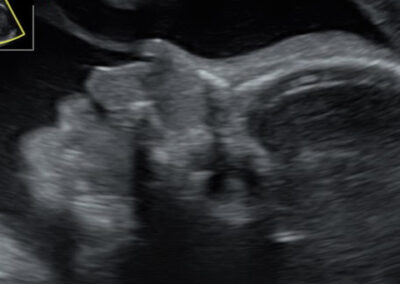

גלריה